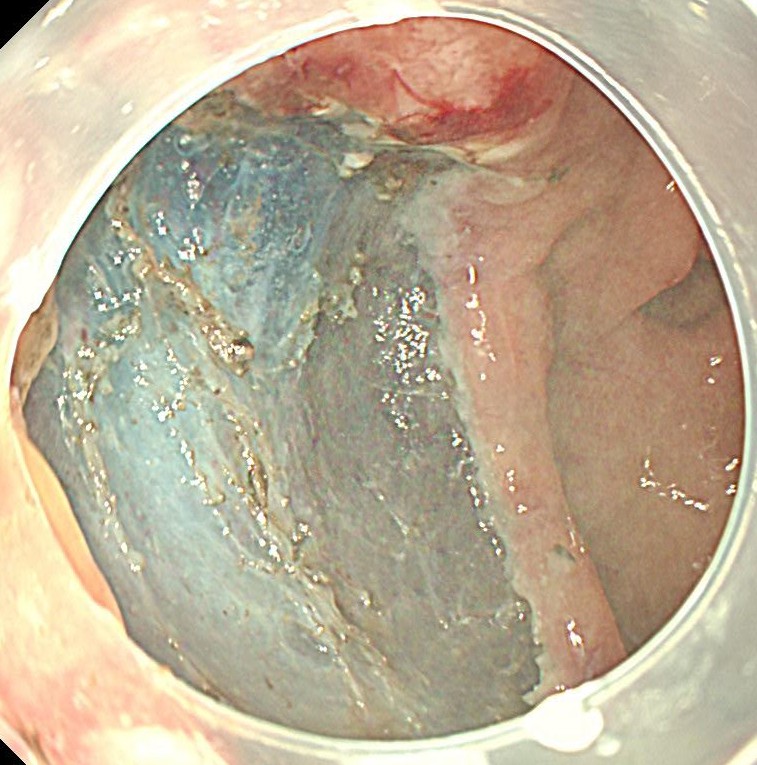

粘膜切除後の欠損部です。この後、1ヶ月間、胃薬を内服してもらいます。

切除標本です。高分化型粘膜内癌であり、根治切除と診断されました。